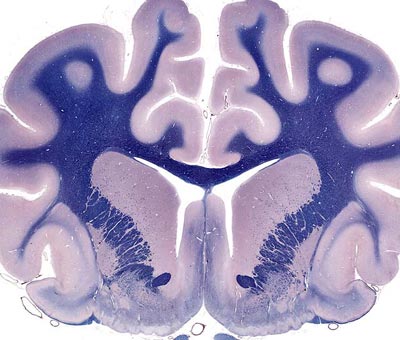

Level 1: Frontal Lobes